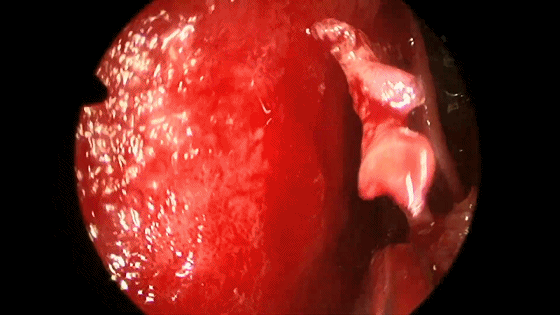

▼咬骨钳咬除碎骨。

▼咬钳去除蝶窦黏膜,若出现黏膜渗血,可用小棉片将黏膜推开或电灼黏膜使其皱缩。蝶窦黏膜不必完全切除。

▼继续磨除蝶窦前壁骨质。 定位蝶窦中线。